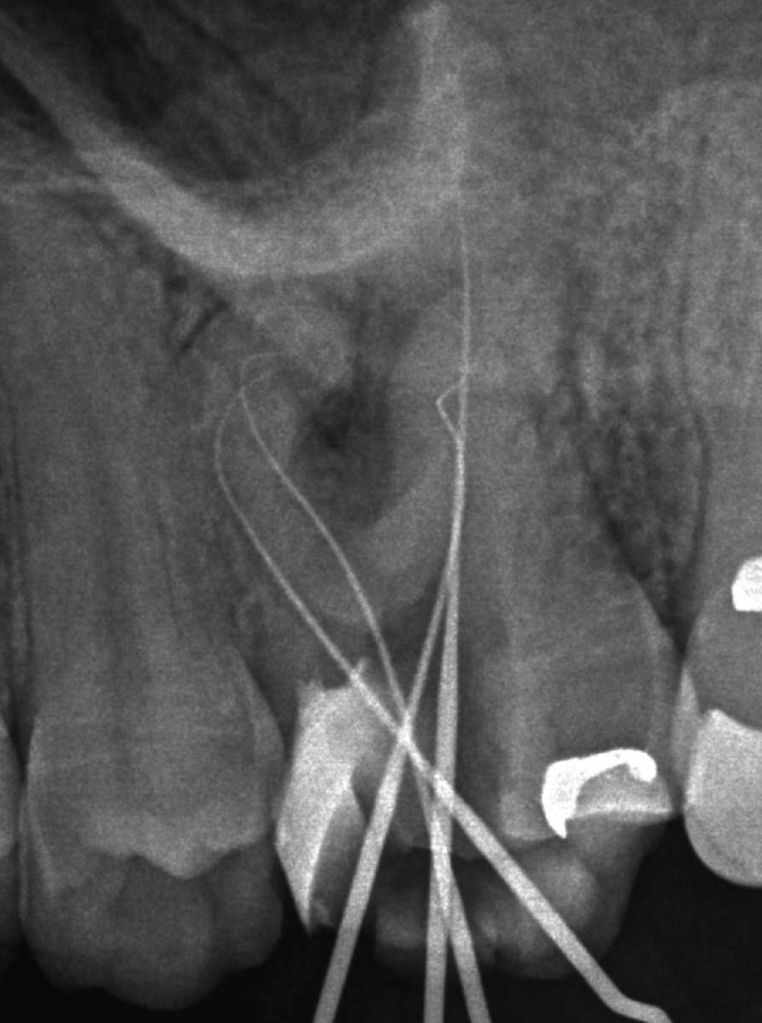

Reconstrucción preendodóntica

Reco pared vesticular